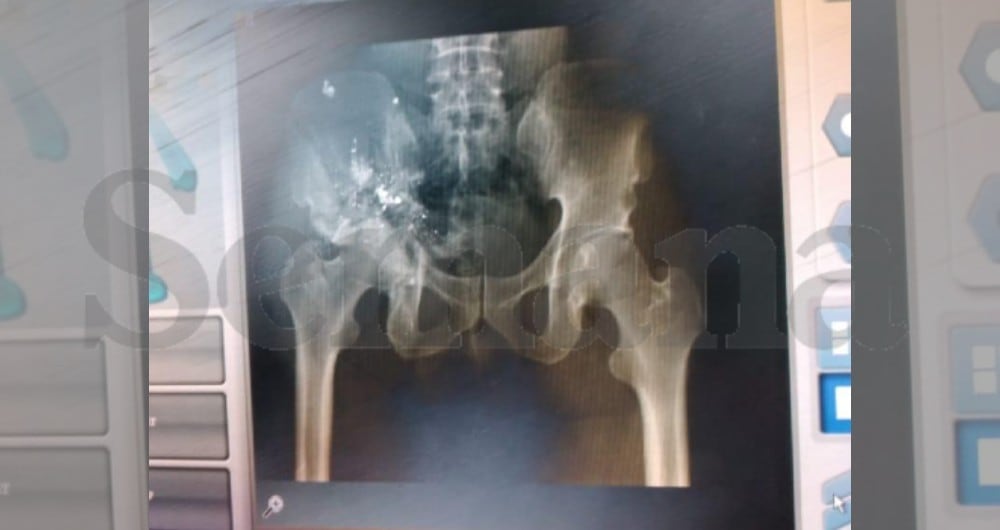

Otras placas muestran sus extremidades fracturadas, al igual que su cadera. Desde los primeros días, las autoridades de Haití han sostenido que el presidente Moïse fue torturado por los mercenarios que lo asesinaron, presuntamente con el objetivo de hacerlo firmar su renuncia.

El informe forense había relatado de una manera muy cruda la escena del crimen que vio esa madrugada del 7 de julio: “Lo encontramos acostado boca arriba: pantalón azul, camisa blanca manchada de sangre, boca abierta, ojo izquierdo perforado. Vimos un agujero de bala en la frente, uno en cada pezón, tres en la cadera, uno en el abdomen”.